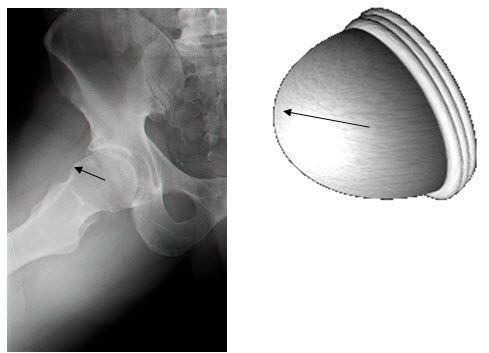

באופן כללי, ישנם שני סוגים עיקריים של תפס: האחד נובע מבליטה של ראש הפמור ונקרא cam type, והשני נובע מבליטת הקיר של פתח המכתש האצטבולרי ונקרא Pincer type. בנוסף, חלק ניכר ממקרי התפס נגרמים משילוב של שני סוגים אלו.

צילום רנטגן שמדגים תפס מסוג cam ומודל תלת מימדי הממחיש את הבעיה בתנועה של ראש ירך עם בליטה המשנה את הצורה העגולה שלו